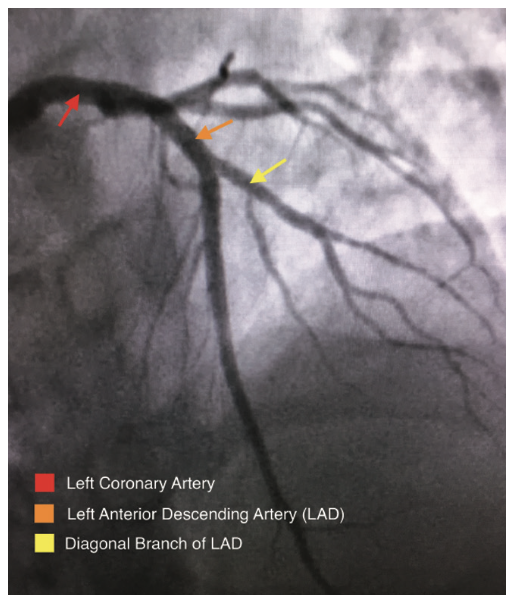

A coronary angiogram was performed, revealing a critical bifurcation stenosis of the mid left anterior descending artery (LAD) and a large diagonal branch vessel which was felt to be the culprit vessel causing her symptoms (Figure 3). Using the CorPath from a 6 French radial approach, a guidewire was placed across the lesion into the diagonal branch of the LAD and a second guidewire was placed across the lesion into the mid LAD (Figure 4). After pre-dilating the lesion, the CorPath was used to measure the longitudinal length of the diagonal branch at the ostium. An appropriately sized Tryton stent was placed over the diagonal branch guidewire and advanced to the site of the lesion. The stent was then carefully advanced by utilizing the CorPath such that the mid-markers precisely straddled the ostium of the diagonal branch to within 1 mm (Figure 5). The Tryton stent delivery system balloon was inflated and the stent was successfully deployed in an appropriate position (Figure 6). The Tryton stent balloon was withdrawn and the diagonal branch guidewire was rewired through the transition zone of the Tryton stent into the main vessel distal to the ostium of the diagonal branch, taking care not to retract proximal to the Tryton stent. Once the guidewire was successfully placed in the LAD through the transition zone, the “trapped” original LAD guidewire was removed (Figure 7). The length needed for the LAD stent was measured from the proximal edge of the Tryton stent to beyond the distal edge of the LAD lesion, and a drug-eluting stent (DES) was advanced over the same guidewire into position within the main branch zone of the Tryton stent and extending into the LAD, and then deployed. After removal of the DES balloon, an additional guidewire was selected and advanced into the diagonal branch, taking care to ensure that it was advanced within the lumen of the LAD stent. Two appropriately sized balloons were selected and advanced into position in the diagonal branch and LAD along their respective guidewires. Simultaneous kissing balloon inflation was performed (Figure 8). Repeat angiography confirmed adequate stent expansion and demonstrated dramatic improvement in coronary perfusion (Figure 9).